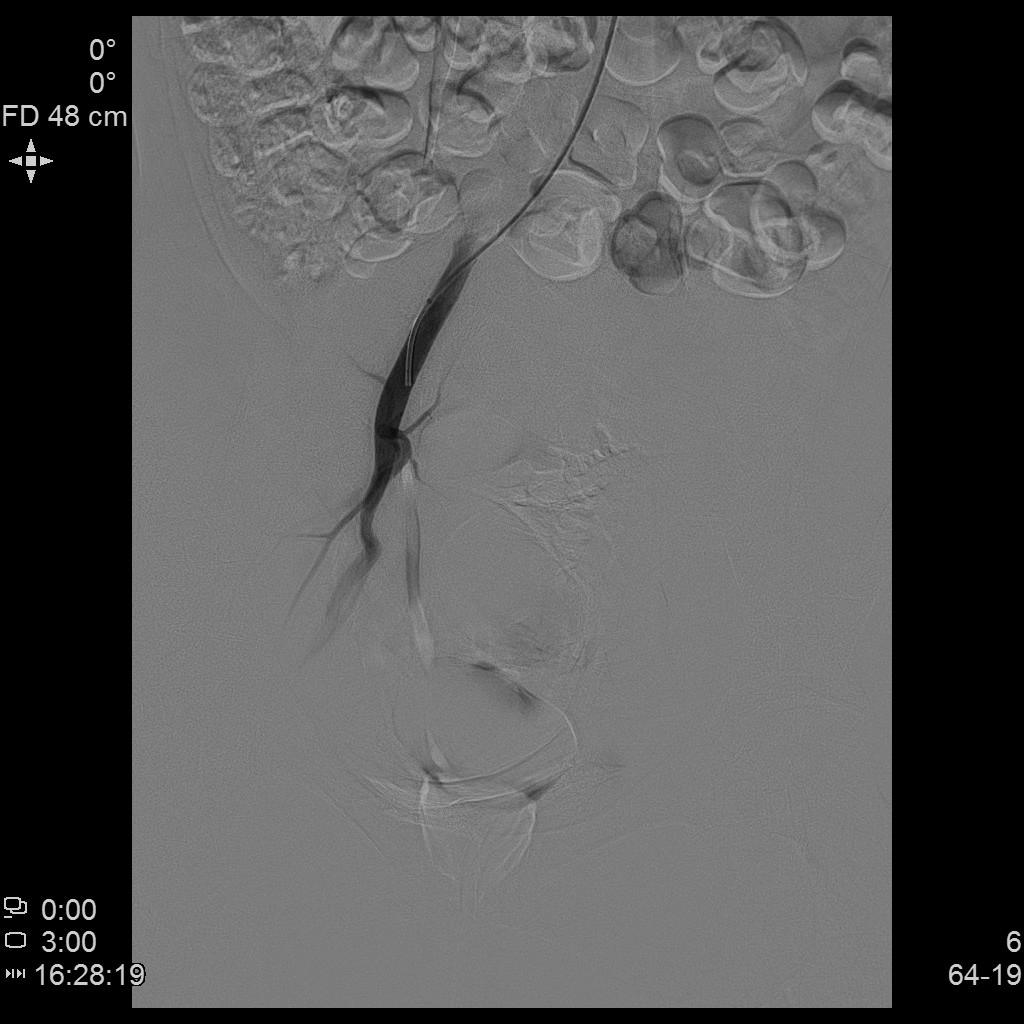

- 栓塞术后复查造影显示右侧子宫动脉分支末梢未见显示

- 进一步超选插管左侧子宫动脉造影确认位置

- 微导管进一步超选插管左侧子宫动脉主干造影确认位置